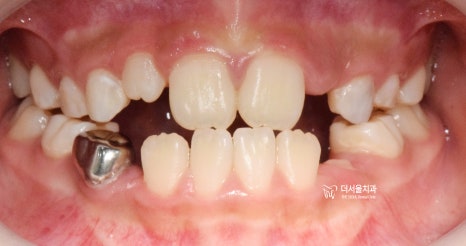

정면 사진 및 측면 안모 사진에서,

느껴지는 것들이 있습니다.

첫번째, 주걱턱의 경향

두번째, 얼굴이 길게 느껴짐

얼굴이 길게 느껴지는 거는,

사진으로만 봤을 때는 치아의 문제입니다.

즉, 교합 관계만 올바르게 맞춰주면

아래턱이 위로 올라갈 거 같네요.

다만, 주걱턱의 경향은 골격성의 문제기 때문에

성장교정 을 통해서 위턱과 아래턱의

균형이 맞아야 개선이 되는 상황이였습니다.